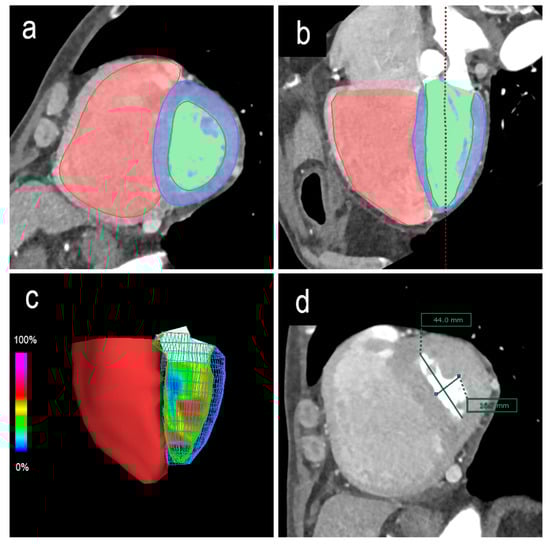

2.5. Image Analysis

Biventricular functions were analyzed using a three-dimensional image analysis application (SYNAPSE VINCENT version 4.3.0003; Fujifilm, Tokyo, Japan). Based on the multiphase reconstruction CT images, end-diastole was defined as 0% of the RR interval, and end-systole was defined as the minimal ventricular volume. The contours of the ventricular lumens at end-diastole and end-systole were semi-automatically or manually traced, and end-diastolic volume (EDV), end-systolic volume (ESV), and ejection fraction (EF) were automatically calculated using Simpson’s method (Figure 1a–c). Since the left ventricle in the end-systolic phase is frequently subjected to morphological displacement, the short-axis centers of the left ventricles were adjusted slice by slice. The papillary muscles were included in the myocardium and excluded from the ventricular volume.

The LV end-diastole index (edEI) and end-systole eccentricity index (esEI) were measured on short-axis images at the level of the papillary muscles as follows: EI = D2/D1 (Figure 1d).

Figure 1. Biventricular end-diastolic and end-systolic volumes and ejection fractions calculated using Simpson’s method. The contours of the ventricular lumens are semi-automatically or manually traced along the short axis (a) or long axis (b). Three-dimensional reconstruction image of the ventricles (c). The eccentricity index is measured on short-axis images at the level of the papillary muscles. In this case, the end-systole eccentricity index (esEI) is the diameter rate of D2/D1 (d). D1 = the septal-lateral endocardium distance perpendicular to the septum. D2 = the anterior-inferior endocardium distance parallel to the septum.